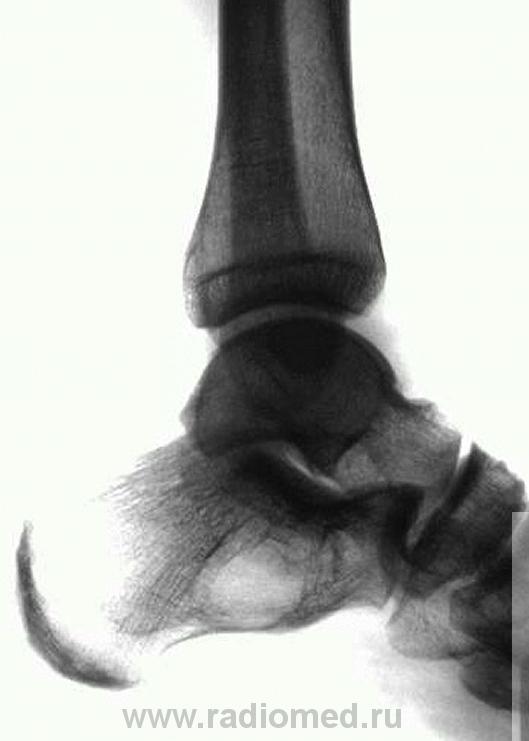

а это снимок справа

Мы довольно часто встречаемся с такой патологией - костная киста, при проведении экспертизы годности к военной службе, при рентгенометрии "продольного плоскостопия", и довольно часто это патологическое состояние бывает с одной стороны.

киста пяточной кости и вальгусная деформация голеностопного сустава

1- псевдокиста пяточной кости, данная локализация характерная, но клинику она обычно не даёт а если и дает то редко, я уже выкладывал случай: